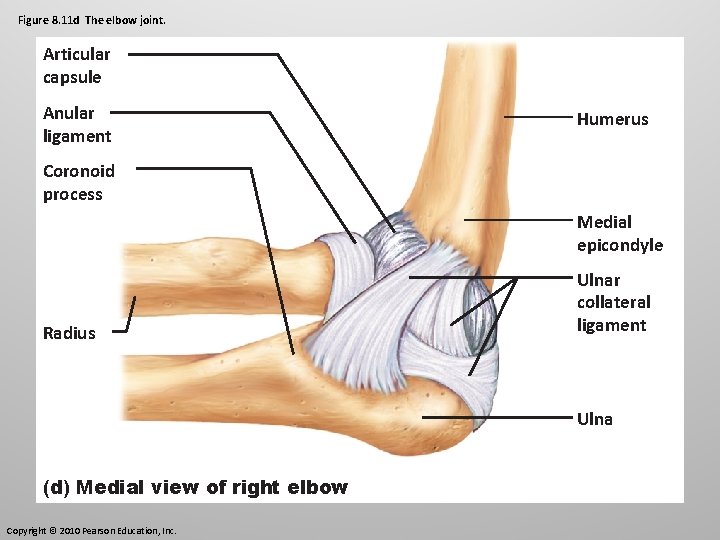

Elbow Joint This is a hinge joint where the radius and ulna articulate with the condyles of the humerus. The ulna’s trochlear notch forms a tight hinge with the trochlear of the humerus. This articulation allows for flexion and extension only.

Elbow Joint Side to side movement is prevented by the ulnar collateral ligament (triangular) and radial collateral ligament.

Figure 8. 11 d The elbow joint. Articular capsule Anular ligament Humerus Coronoid process Medial epicondyle Radius Ulnar collateral ligament Ulna (d) Medial view of right elbow Copyright © 2010 Pearson Education, Inc.